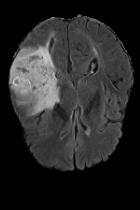

Current unsupervised anomaly localization approaches rely on generative models to learn the distribution of normal images, which is later used to identify potential anomalous regions derived from errors on the reconstructed images. However, a main limitation of nearly all prior literature is the need of employing anomalous images to set a class-specific threshold to locate the anomalies. This limits their usability in realistic scenarios, where only normal data is typically accessible. Despite this major drawback, only a handful of works have addressed this limitation, by integrating supervision on attention maps during training. In this work, we propose a novel formulation that does not require accessing images with abnormalities to define the threshold. Furthermore, and in contrast to very recent work, the proposed constraint is formulated in a more principled manner, leveraging well-known knowledge in constrained optimization. In particular, the equality constraint on the attention maps in prior work is replaced by an inequality constraint, which allows more flexibility. In addition, to address the limitations of penalty-based functions we employ an extension of the popular log-barrier methods to handle the constraint. Comprehensive experiments on the popular BRATS'19 dataset demonstrate that the proposed approach substantially outperforms relevant literature, establishing new state-of-the-art results for unsupervised lesion segmentation.